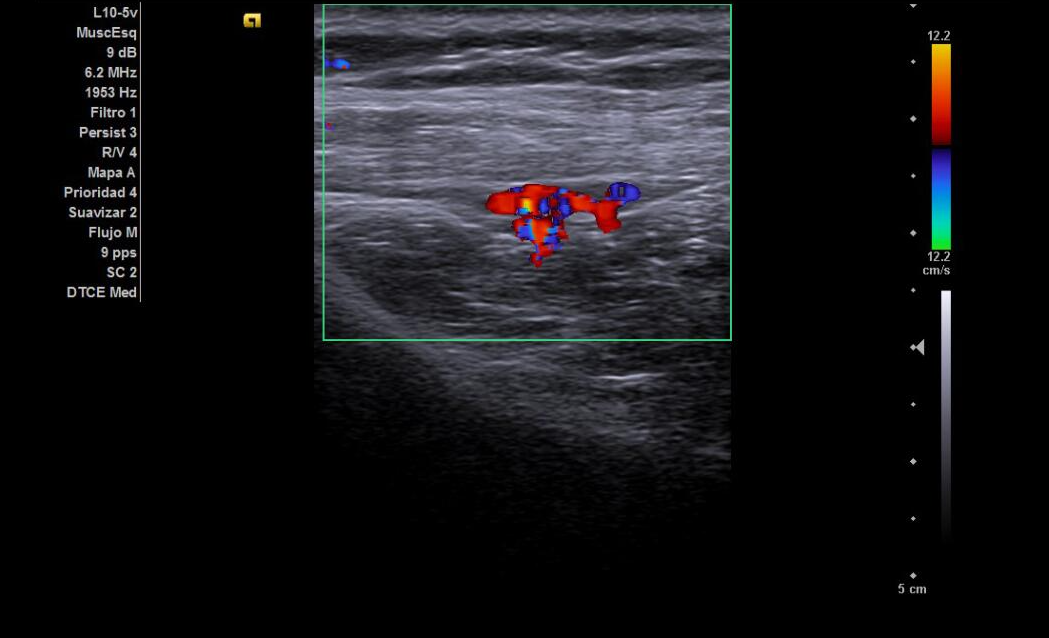

Hallazgos ecográficos

Tendones supra e infraespinoso normales; bursa fina; cabeza larga del bíceps normal. Nervio supraescapular discretamente hipoecoico y engrosado en la escotadura; sin colecciones. Sin signos de pinzamiento dinámico.

Analgesia, relajantes musculares y fisioterapia. Ante la no mejoría, infiltración ecoguiada del nervio supraescapular (1 ml trigon + 4 cc anestésico local). Sin incidencias.